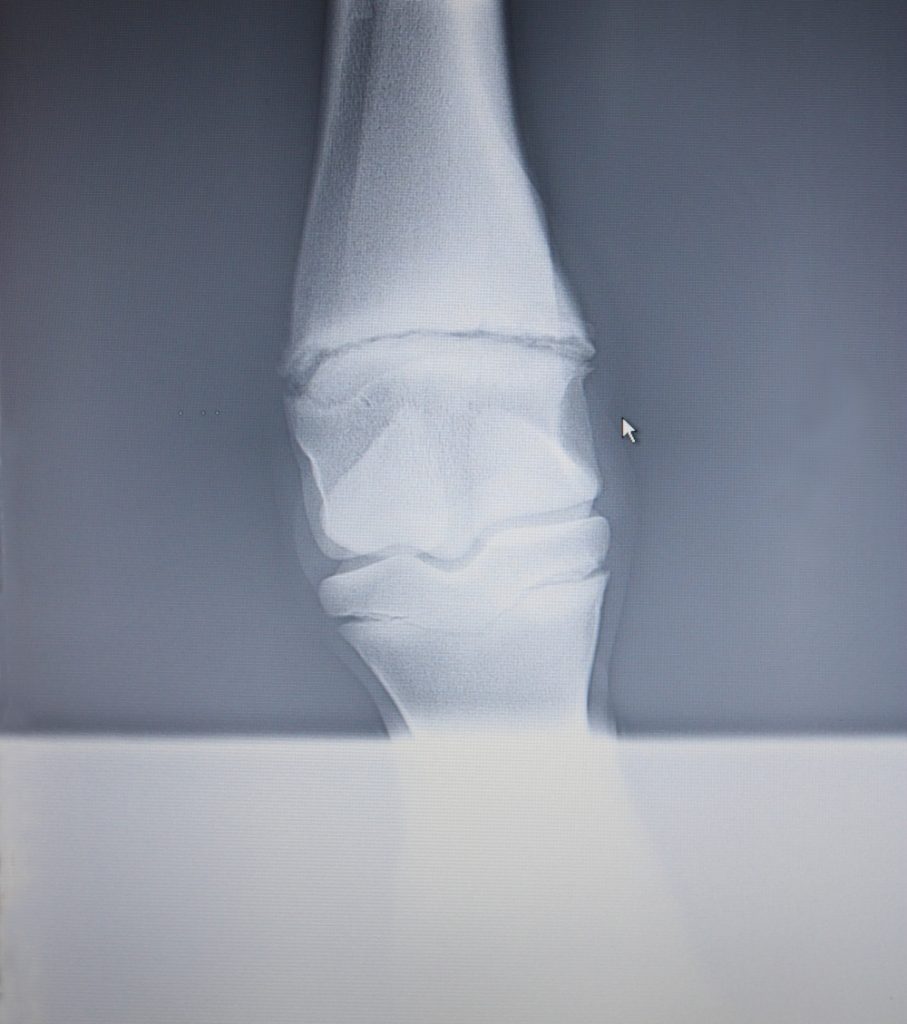

The greater part of managing foal development is affected by diet, exercise and how well the foal thrives on the mare, but there is a fine balance that can easily be tipped the wrong way resulting in deformity. The farrier’s role is highly valuable in maintaining, detecting and correcting deviations from the norm, when necessary. These conditions are divided into angular limb deformity (ALD ) and flexural deformity (FD). Beginning with ALD , deviation from the normal alignment of the foal limb either medially or laterally. (This is not limb rotation, which is untreatable by the farrier.) These conditions may be present at parturition and could be congenital, or are acquired as the foal develops, often when the foal is growing rapidly.